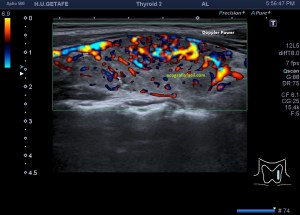

En la exploración objetivamos una glándula tiroidea aumentada de tamaño, sin imágenes nodulares, pero si heterógenea toda ella con afectación global en ambos lóbulos tiroideos. Semiológicamente se observa una y/o hiperplasia glandular y es muy significativo un abombamiento anterior de la glándula, con unas medidas elevadas discretamente respecto de sus medidas en rango de normalidad, es decir, la paciente tiene bocio no nodular y además alteración en la ecogenicidad de la glándula, pero lo más llamativo fue cuando puse el doppler para estudiar la vascularización de ambos lóbulos tiroideos. Era una vascularización elevada, mucho más que la normal vascularización de esta glándula. Es el conocido Infierno Tiroideo.

Cuando estudiamos concienzudamente la ecoarquitectura del Tiroides es momento de estudiar su apariencia vascular y descubro esto inmediatamente que me llama poderosamente la atención y que ves en la imagen 5, mira:

5

En la imagen 6 observas la misma imagen con el modo angio activado (doppler power), con el que vamos a conseguir observar la vascularización de flujo lento, por eso en el mismo corte puedes ver como si hubiera más vascularización que ves en la imagen 5.

6

En la imagen 7 tienes el corte del lado contralateral del tiroides, donde con el modo angio activado, puedes ver además que ese lóbulo tiene más actividad vascular que el izquierdo.

7